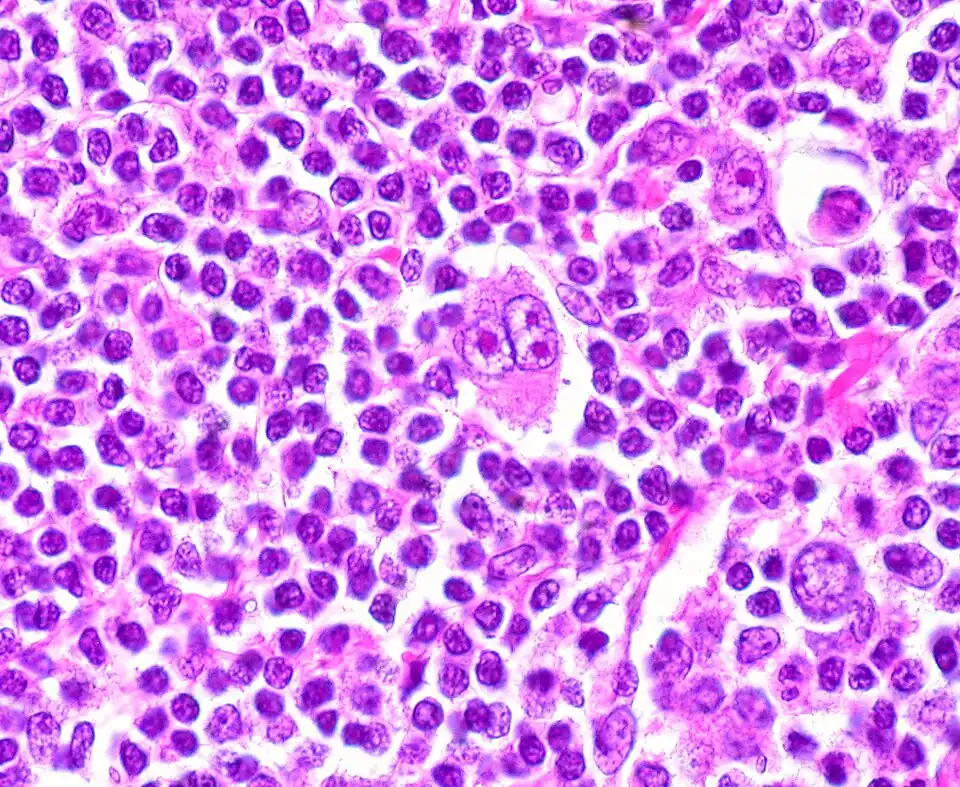

O linfoma de Hodgkin clássico é um linfoma de células B caracterizado pela presença de algumas células gigantes multinucleadas de Hodgkin e Reed-Sternberg.[1] Estas células constituem menos de 1% do tecido linfoide infiltrado e estão rodeadas por células inflamatórias que formam o microambiente tumoral.[1][2] As células de Hodgkin e Reed-Sternberg expressam o marcador de superfície CD30, definindo assim o linfoma de Hodgkin clássico. A doença divide-se nos subtipos: